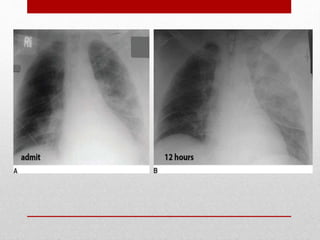

Hemothorax and

Pneumothorax - most

common injuries from both

blunt and penetrating

thoracic trauma